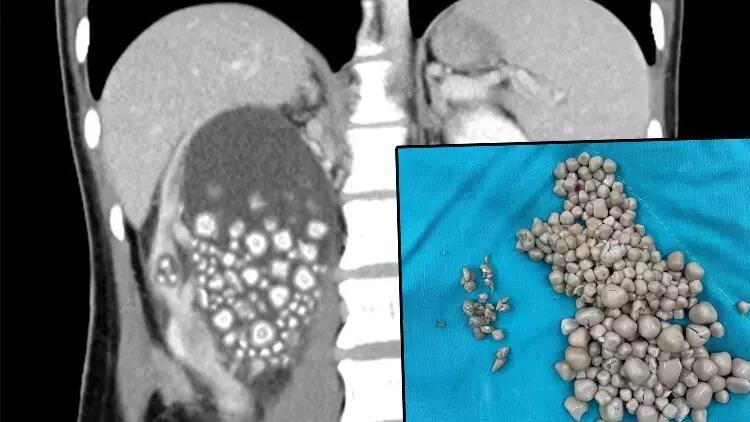

Tayvanın Tainan şəhərində bel ağrısı şikayəti ilə xəstəxanaya müraciət edən 20 yaşlı Xiao Yunun böyrəklərindən 300-dən çox daş çıxarılıb.

Publika.az xəbər verir ki, müayinələr nəticəsində onun böyrəklərində çoxlu böyrək daşı aşkarlanıb. Yu təcili cərrahiyyə əməliyyatına aparılıb. Uğurlu əməliyyatdan sonra Yunun böyrəklərindən 0,5-2 sm ölçüdə 300-dən çox daş çıxarılıb.

Əməliyyatın aparıldığı Chi Mei Xəstəxanasından verilən açıqlamada Yunun su içməyi sevmədiyi və yalnız şəkərli içkilər və çay qəbul etdiyi bildirilib.

Digər tərəfdən, Chi Mei Xəstəxanasının uroloqu Lin Tsai-yang, Tayvanda kişilərin yüzdə 14,9 və qadınların yüzdə 4,3-də böyrək daşı əmələ gəlməsi ehtimalının olduğunu qeyd edib .